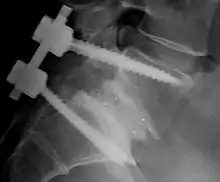

L’arthrodèse postérolatérale instrumentée avec vissage pédiculaire est devenue l’intervention de référence [19, 95, 99, 100, 108]. Elle s’accompagne d’exploration intra canalaire en cas de trajet radiculalgique avec imagerie concordante [33]. La position opératoire en appui sur les deux genoux, cuisses fléchies sur "table à sciatique", permet la mobilisation du bassin sur les têtes fémorales tout en libérant la traction imposées par le psoas au rachis lombaire Les questions qui se posent sont :

Il faut libérer le “ crochet pédiculaire ” à l’origine de conflit radiculaire : le bord inférieur du pédicule est épaté au niveau de la lyse comme l’est une pseudarthrose hypertrophique. Il est recourbé en crochet qui vers le bas emmène la racine L5 avec le déplacement vers l’avant du corps vertébral, à l’origine de conflit. La libération radiculaire impose de suivre la racine sous le pédicule en réséquant le “ crochet ” à la Kerisson de la façon la plus complète possible. La longueur de pédicule restant permet de réaliser le vissage pédiculaire à condition d’insérer la vis dans la partie supérieure du pédicule qui est assez haut.